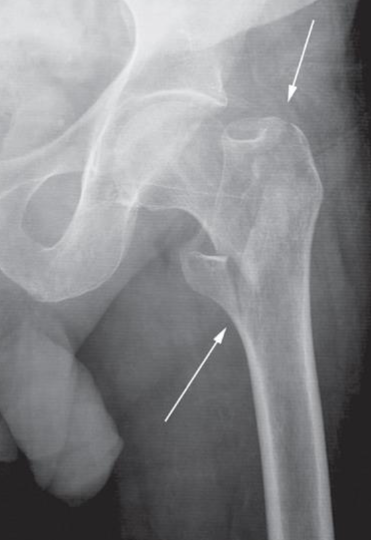

Impacted femoral neck

fracture (arrows) causing only a

sclerotic line and disruption of

the trabecular architecture.

Intertrochanteric fracture

(arrows) between the greater

and lesser trochanters